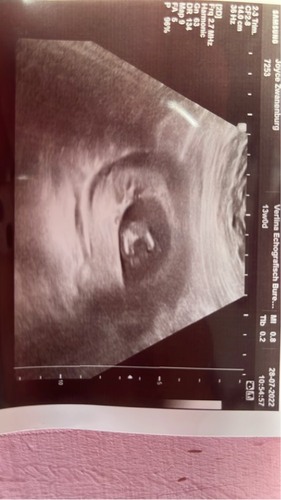

Wij hadden met 13 weken 3 dagen een geslachtsbepaling. Hieruit kwam naar voren dat het een meisje wordt.

Daarna de 13 weken echo met 14 weken en 4 dagen. Ik zag het zelf (wist nu natuurlijk waar ik op moest letten) en benoemde het, toen zei de echoscopiste we kunnen er inderdaad niet omheen dat het een meisje wordt.

Vanaf 13 weken kunnen ze het geslacht al zien. 13- 14 weken is met 98 procent zekerheid.

Ik heb het gezien, en je zag het heel duidelijk, als je weet waar je moet kijken natuurlijk. De technologie van tegenwoordig is niet te vergelijken meer met vroeger. Het echo apparaat van de pretecho is nog beter dat die van de verloskundige.

Wij wisten het geslacht al via de nipt (belgie) en bij de 13 weken echo zag je dit heel duidelijk bevestigt.

De dame die de echo deed gaf aan dat hoe slanker je bent hoe duidelijker/meer je ziet op de 13 weken echo. Zij zag het geslacht ook gelijk en twijfelde geen seconde. Dus misschien iets om rekening mee te houden qua verwachting.

Bij ons zag je duidelijk een piemeltje uitsteken uit ‘t lichaam. Staat ook duidelijk op foto. Je moet dus wel geluk hebben dat je baby er goed voor ligt/zit. Onze baby was heel actief dus we hebben in dat half uur alle mogelijke kanten kunnen zien!